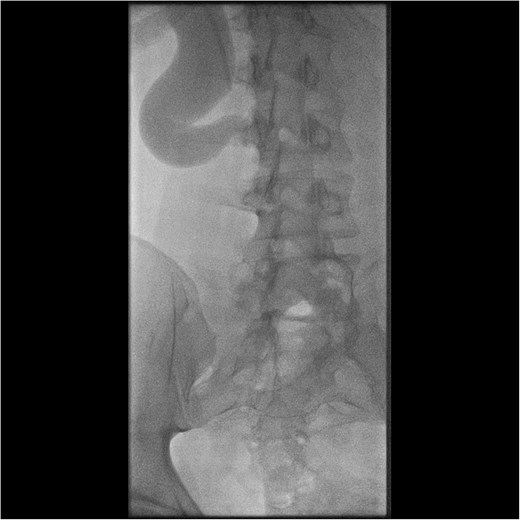

Initial work-up revealed microscopic haematuria and a mildly elevated creatinine of 156 μmol/L (65.4–119.3 μmol/L). A computerized tomogram (CT) urogram showed proximal hydroureteronephrosis with preserved renal cortex (Fig. 1). A diethylenetriamine pentaacetate (DTPA) renogram with diuretic showed accumulation of contrast then prompt excretion with administration of diuretic, suggesting partial obstruction or hypotonic collecting system (Fig. 2). At this point alternative diagnoses were considered, including RU. Ongoing severe right flank pain was noted despite multimodal analgesia and a right-sided nephrostomy was placed with immediate relief of pain and obstruction. Figure 3 shows the nephrostogram with S-shaped hydroureter. No further analgesia was required, and creatinine normalized (90 μmol/L). The case was discussed at a multidisciplinary meeting, wherein a unanimous diagnosis of RU was confirmed, and a plan for minimally invasive laparoscopic dissection and re-anastomosis of the ureter was made.

Interventional image during nephrostomy placement demonstrating S-shaped ureter and clear point of obstruction.